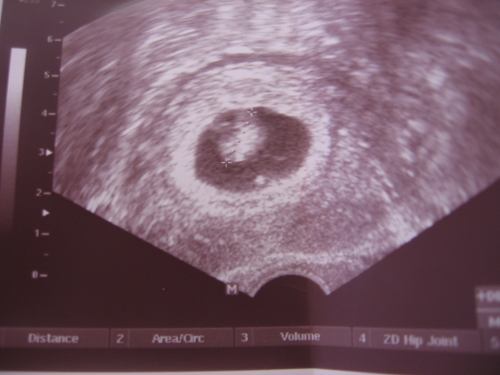

ma voltunk ugye UH-n

Nézte a jobb petefészkemet és elkezdett mérni.

12x11mm, 13x11, 15x13 és 14x12 ... (én közben lélegzetvisszafojtva hallgattam és egyre boldogabb voltam, ahogy hallottam, h már 4 szép van - BMC-ben összesen 5-öt szívtak le) a többi nem mérhető, mert még kicsik.

A bal oldalt nem igazán találta, majd mire sikerült látótérbe hoznia, egyrészt a szemem majd kiugrott, másrészt pedig beíratta a dokinéni, h nem tudja mérni őket, mert csak 2 keze van, de még legalább 1 kéne neki, h lássa őket. Sajnos, a bal oldalam mindig bujkál, de ez van. A lényeg, h tudjuk, h ott is vannak szépek már.